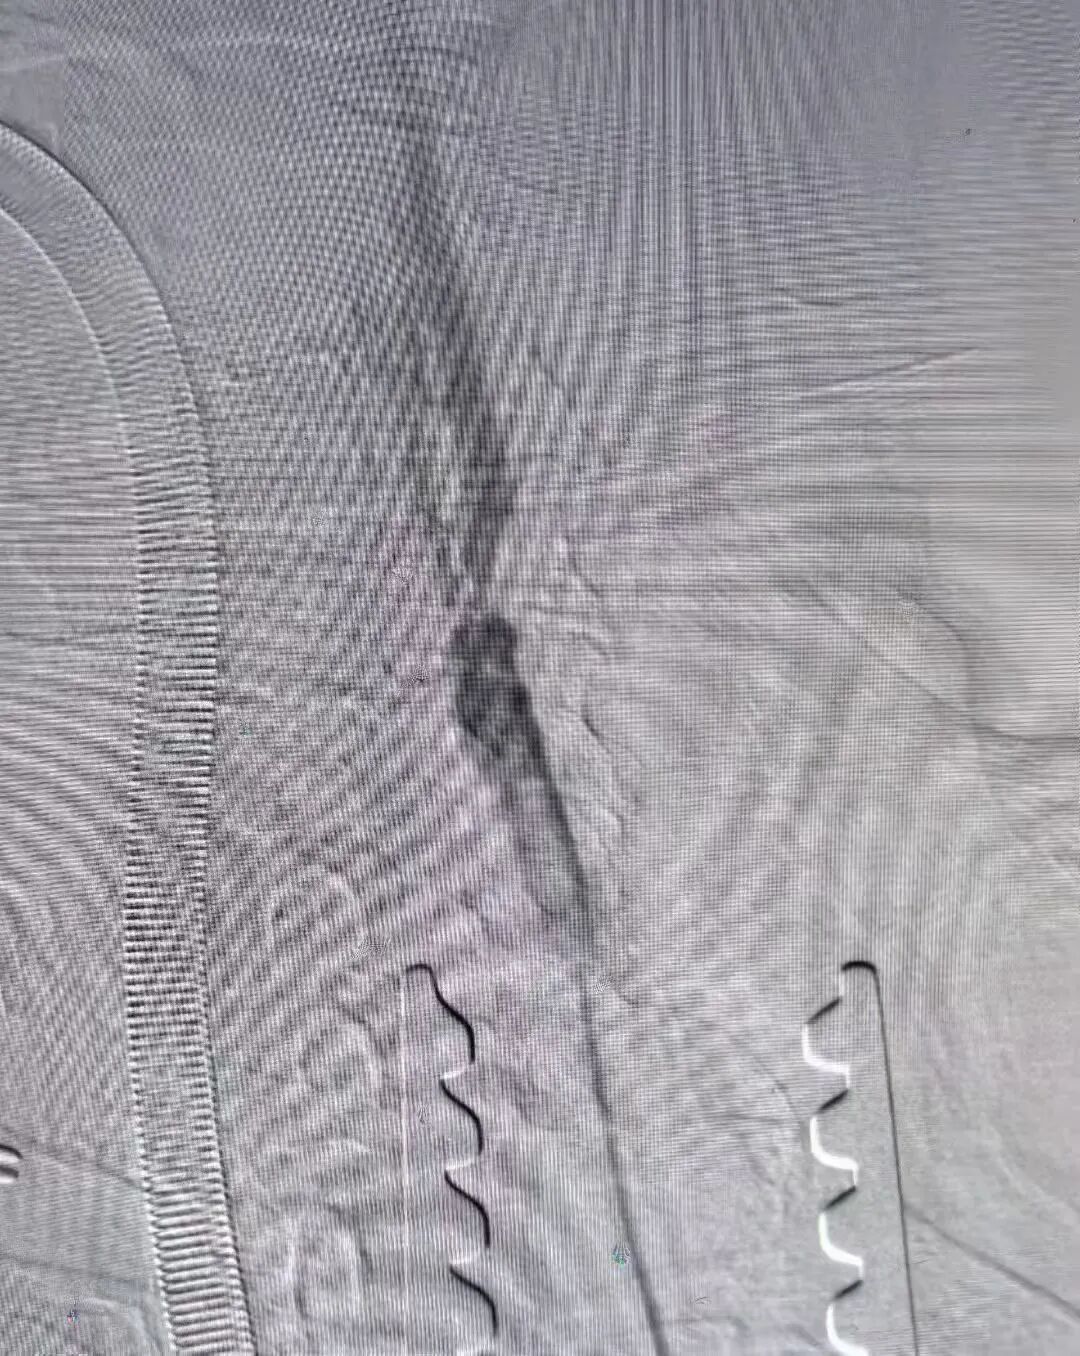

术前及术后造影图像: